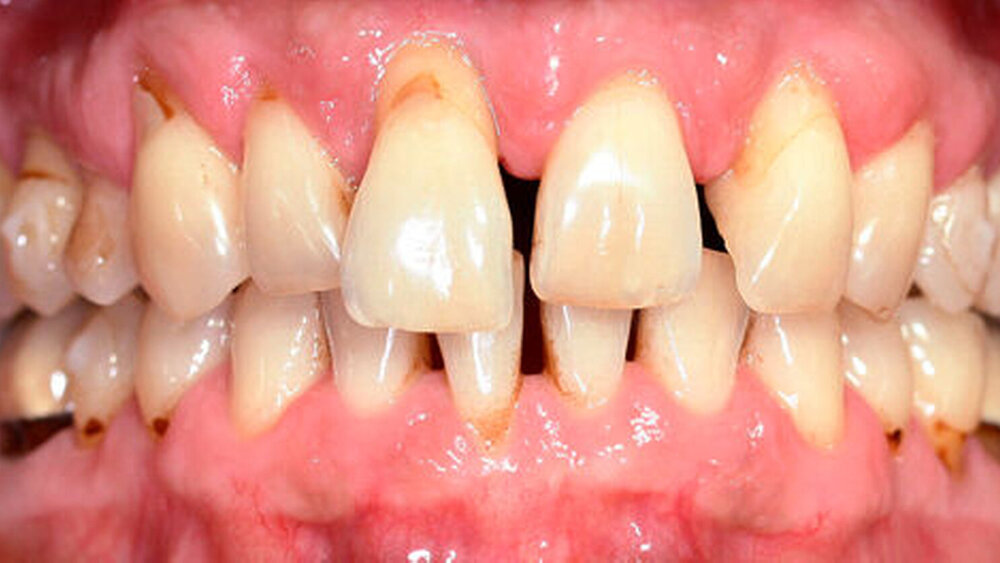

Anamnestisch lagen keine Besonderheiten vor. Es ist jedoch zu vermerken, dass ein regelmäßiger Alkohol-, Koffein- und Nikotinkonsum zugrunde lag. Intraoral zeigte sich ein bereits konservierend versorgtes permanentes Gebiss mit aktivem und inaktivem kariösen Geschehen. Große Anteile der Zahnhälse lagen nach Zahnfleischrückgang in Kombination mit Knocheneinbrüchen frei. Zahn 27 wurde bereits extrahiert.

Eine Beurteilung der parodontalen Situation an Zahn 11 offenbarte mesial und distal Sondierungstiefen von jeweils 6 mm.

Röntgenologisch stellte sich im Orthopantomogramm der bereits intraoral ersichtliche horizontale und vertikale Knochenabbau mit Attachmentverlust an einzelnen Zähnen dar. Die Erhaltungswürdigkeit einzelner Zähne war aufgrund des starken Knochenverlustes beziehungsweise der Beeinträchtigung des Halteapparates als kritisch zu beurteilen.

Zudem wurde die Diagnose einer Parodontitis gestellt, die eine Rücküberweisung an den Hauszahnarzt erforderlich machte (Abbildung 2).